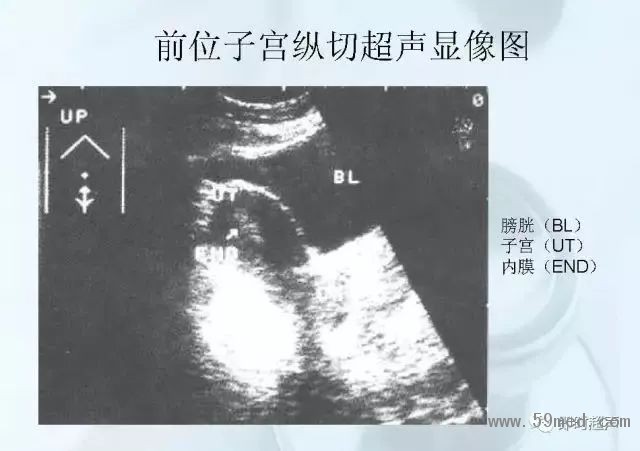

新聞中心 收藏!正常B超解剖圖譜,超實用!

![]() ![]() ![]() ![]() ![]() ![]() ![]() ![]() ![]() ![]() ![]() ![]() ![]() ![]() ![]() ![]() ![]() ![]() ![]() ![]() ![]() ![]() ![]() ![]() ![]() ![]() ![]() ![]() ![]() ![]() ![]() ![]() ![]() ![]() ![]() ![]() ![]() 【注:本文來源于即時超聲,版權(quán)歸原作者所有,如有侵權(quán) 請聯(lián)系 速刪】 =========================== 【閱精彩*悅分享】隨手點擊轉(zhuǎn)至朋友圈,與大家一起分享精彩資訊!當(dāng)然您也可以通過以下方式找到我,與您共同分享藍(lán)韻影像超聲的更多精彩!微信號:landultrasound 電話:+86-0755-66869896 24小時客服熱線:400-888-6452